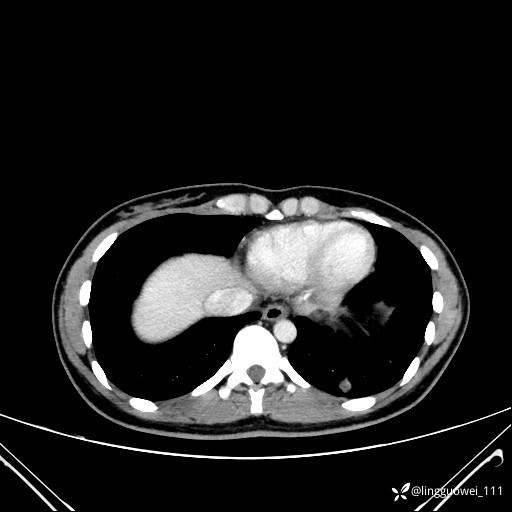

年轻女性咳嗽,CT发现肺结节,良性还是恶性?(4天后公布结果)

患者性别:女

患者年龄:26岁

主诉:咳嗽来诊,结节性质不明。

肺毛细血管瘤 (2)